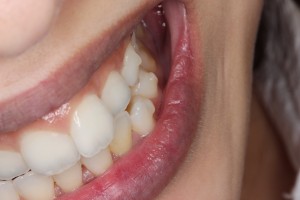

(近くで見るとこんな感じです。膨らんで見える部分がアタッチメントです。)

歯に限りなく近い色をしているので写真で見てもほとんど分かりませんよね!実際も全く気付かれません。

舌で触るとデコボコしているのが分かり、唇に少し当たっている感覚がある感じですが、気にならない程度です。